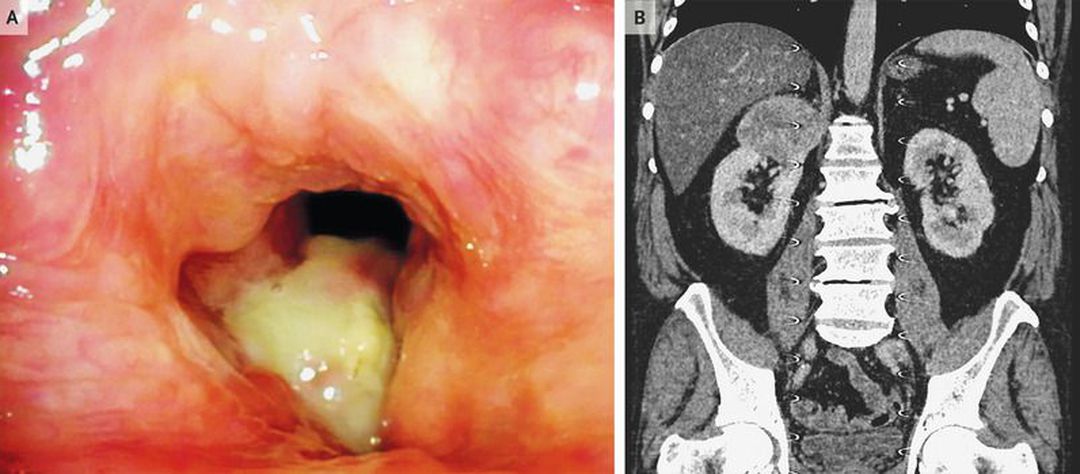

A 49-year-old man was referred to the otorhinolaryngology clinic with a 3-month history of progressive voice changes and pain with swallowing. He had a history of hypertension and type 2 diabetes mellitus and was a current smoker. He had no recent weight loss or other systemic symptoms. Fiberoptic laryngoscopy revealed a 2-cm lesion at the level of the vocal cords (Panel A). The laryngeal lesion was excised, and findings on histologic examination were consistent with metastasis of a clear-cell carcinoma. Computed tomography of the abdomen and chest were subsequently performed and revealed a mass measuring 7.0 cm by 6.4 cm by 6.6 cm at the superior pole of the right kidney (Panel B), several pulmonary lesions, and enlarged mediastinal lymph nodes — findings consistent with metastatic disease. Laparoscopic radical nephrectomy of the right kidney was performed, and oral sunitinib was initiated for the treatment of metastatic renal-cell carcinoma. At 1 year of follow-up, the patient had stable mediastinal lesions and complete remission (disappearance) of some of the pulmonary lesions.